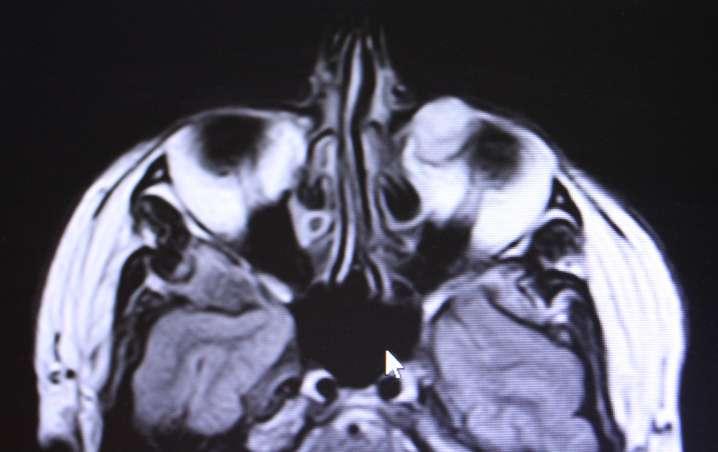

ü Hombre 19 años portador de Leucemia linfatica aguda diagnosticada el 2016, es tratado ese mismo año con trasplante alogénico, sin embargo 4 meses posterior al trasplante sufre una recaída leucémica. Desde entonces el paciente se ha mantenido en QMT sistémica paliativa

ü El año 2017 el paciente evoluciona con enfermedad injerto contra huesped y el 2018 con meningitis leucémica

ü El año 2019 consulta en el policlínico de oftalmología del Hospital del Salvador por disminución de AV ODI de 7 dias evolución, asociado a sensación de cuerpo extraño.

Examen Físico

ü AV con CAE: 20/70 OD y 20/60 OI

ü PIO normal bilateral

ü DPAR en OD

ü Motilidad ocular conservada.

ü BMC: Puntata extensa como consecuencia de efectos adversos producidos por la QMT (Imagen A y B) A